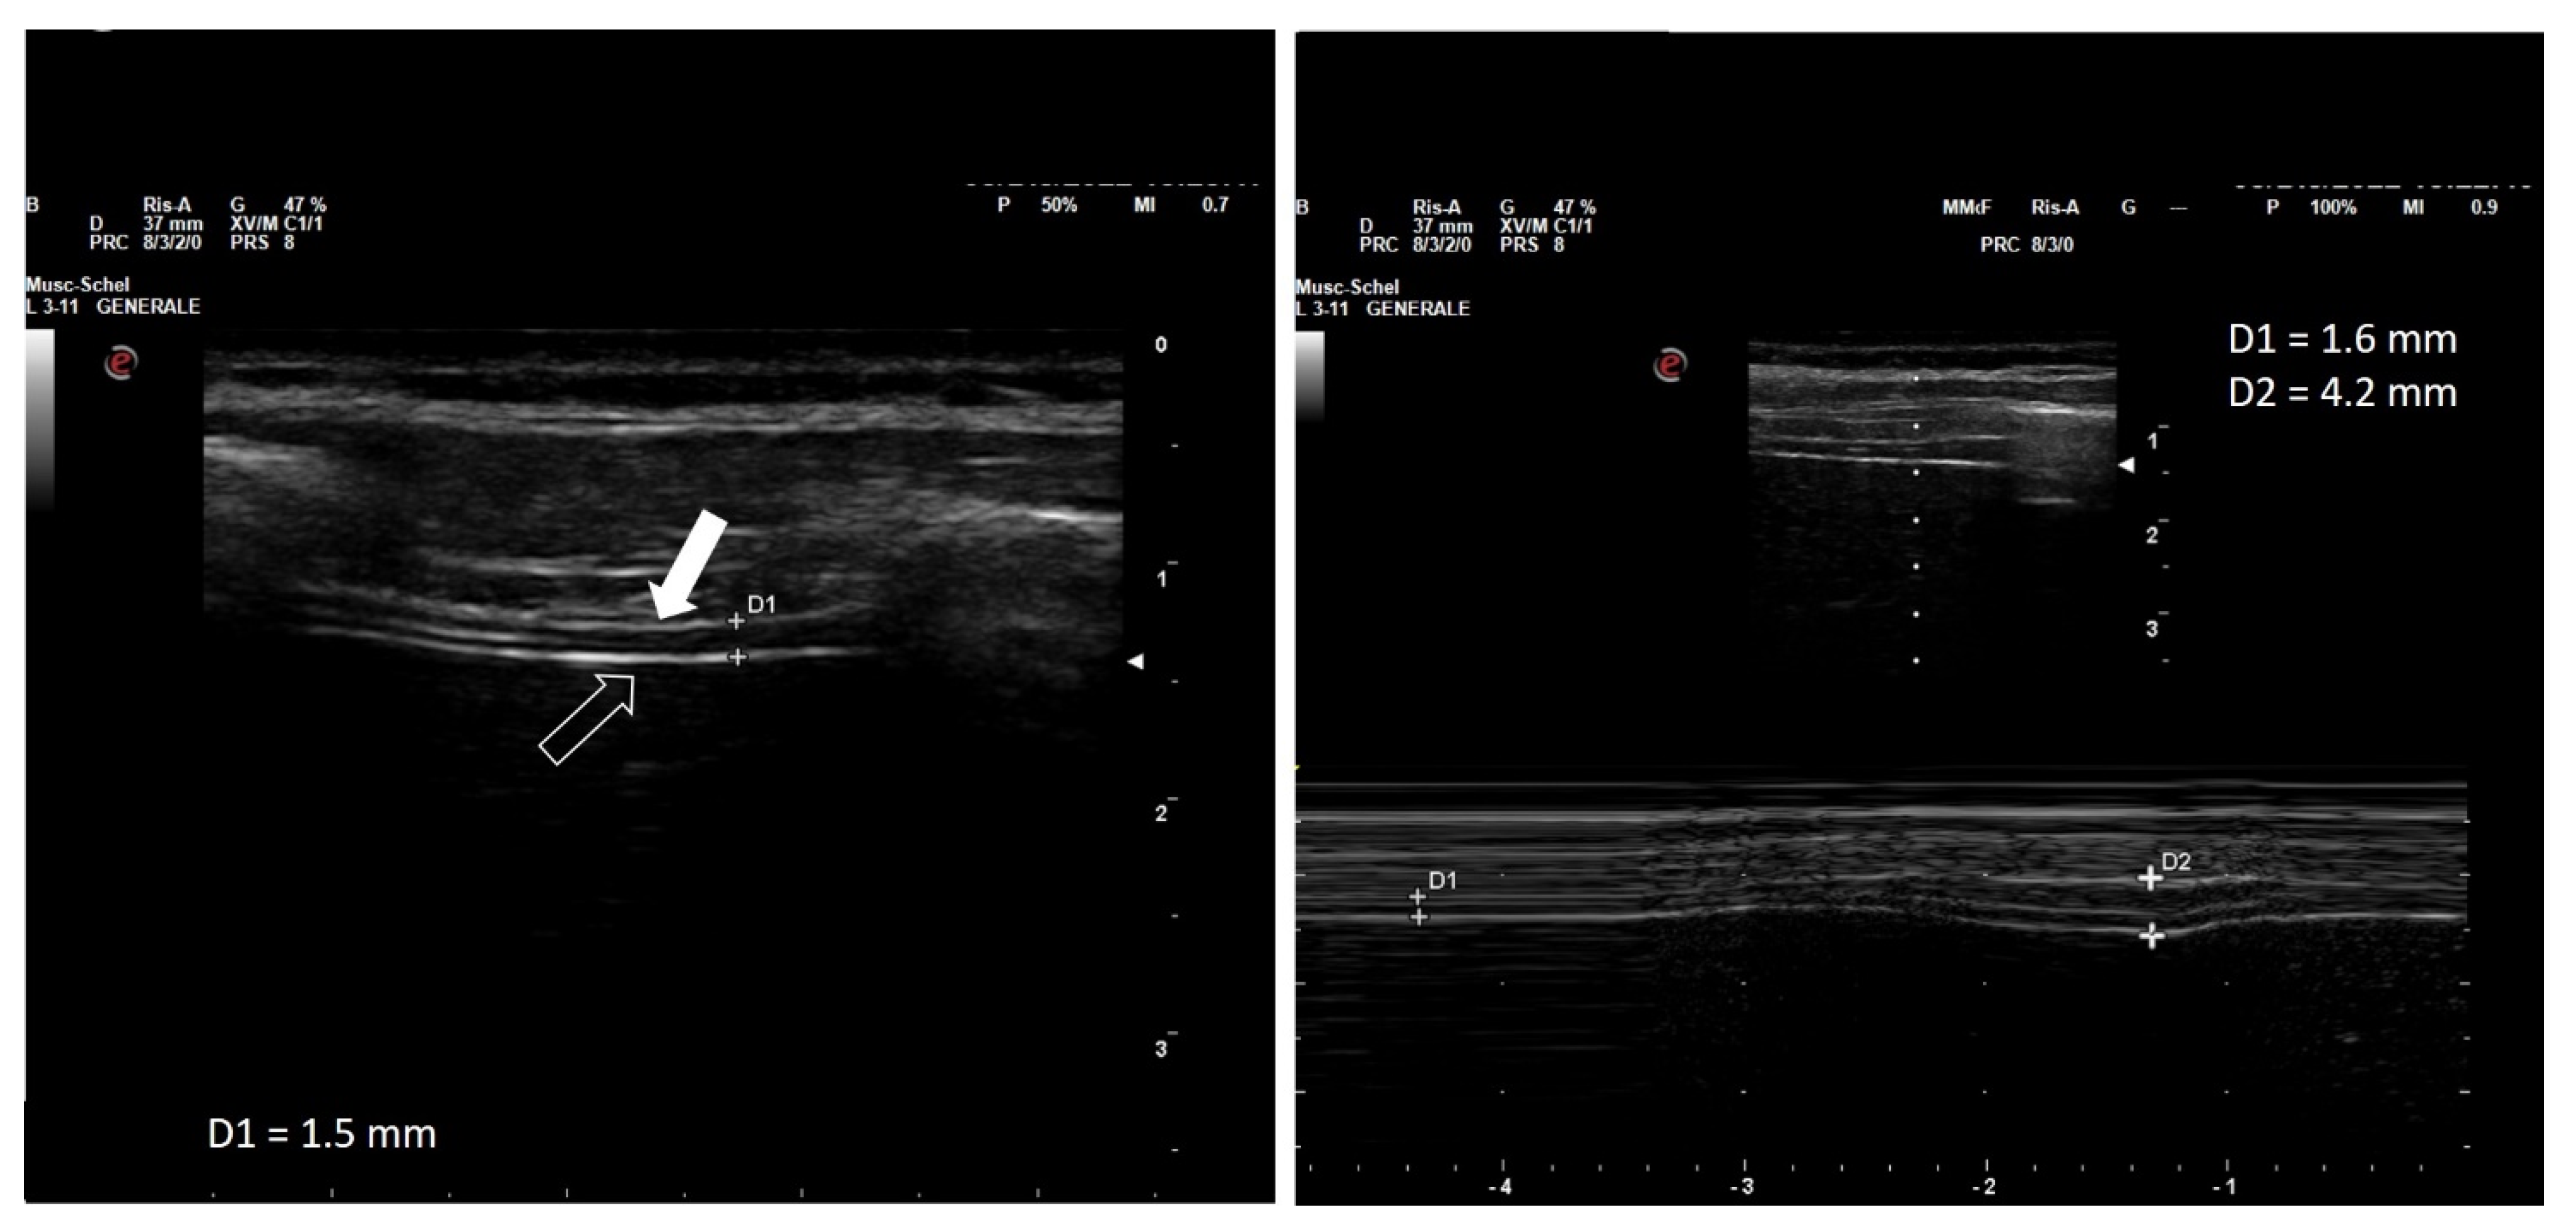

2. Diaphragm Function Assessment

3.1. Clinical Case One

3.2. Clinical Case Two

3.3. Case Discussion